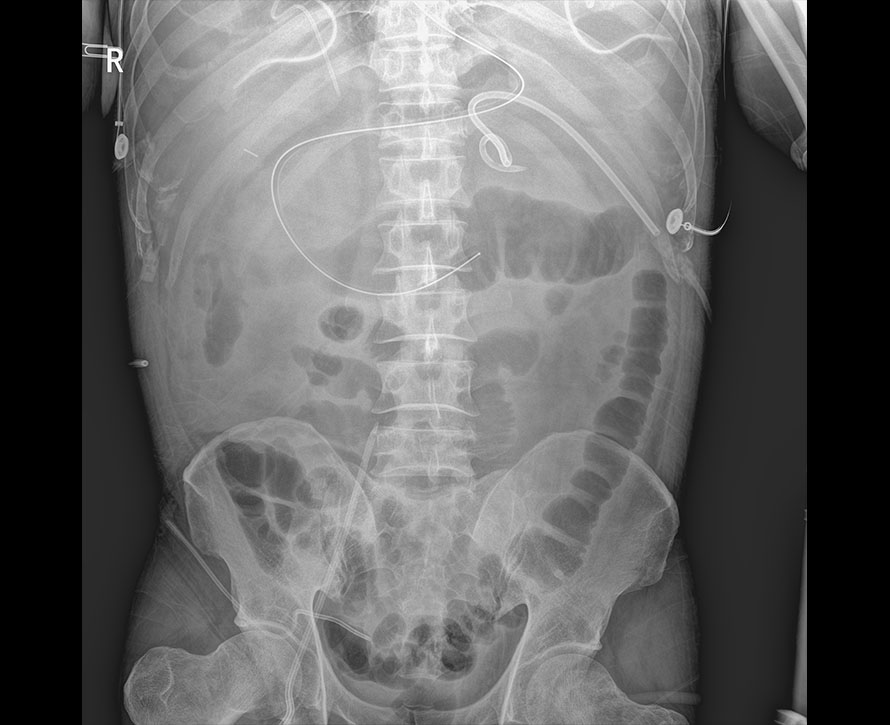

臨床圖像